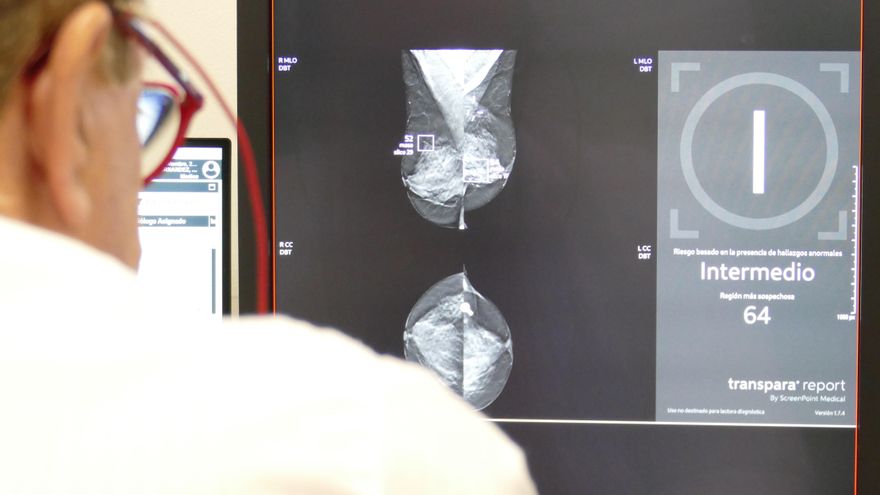

Una mamografía en una imagen de archivo